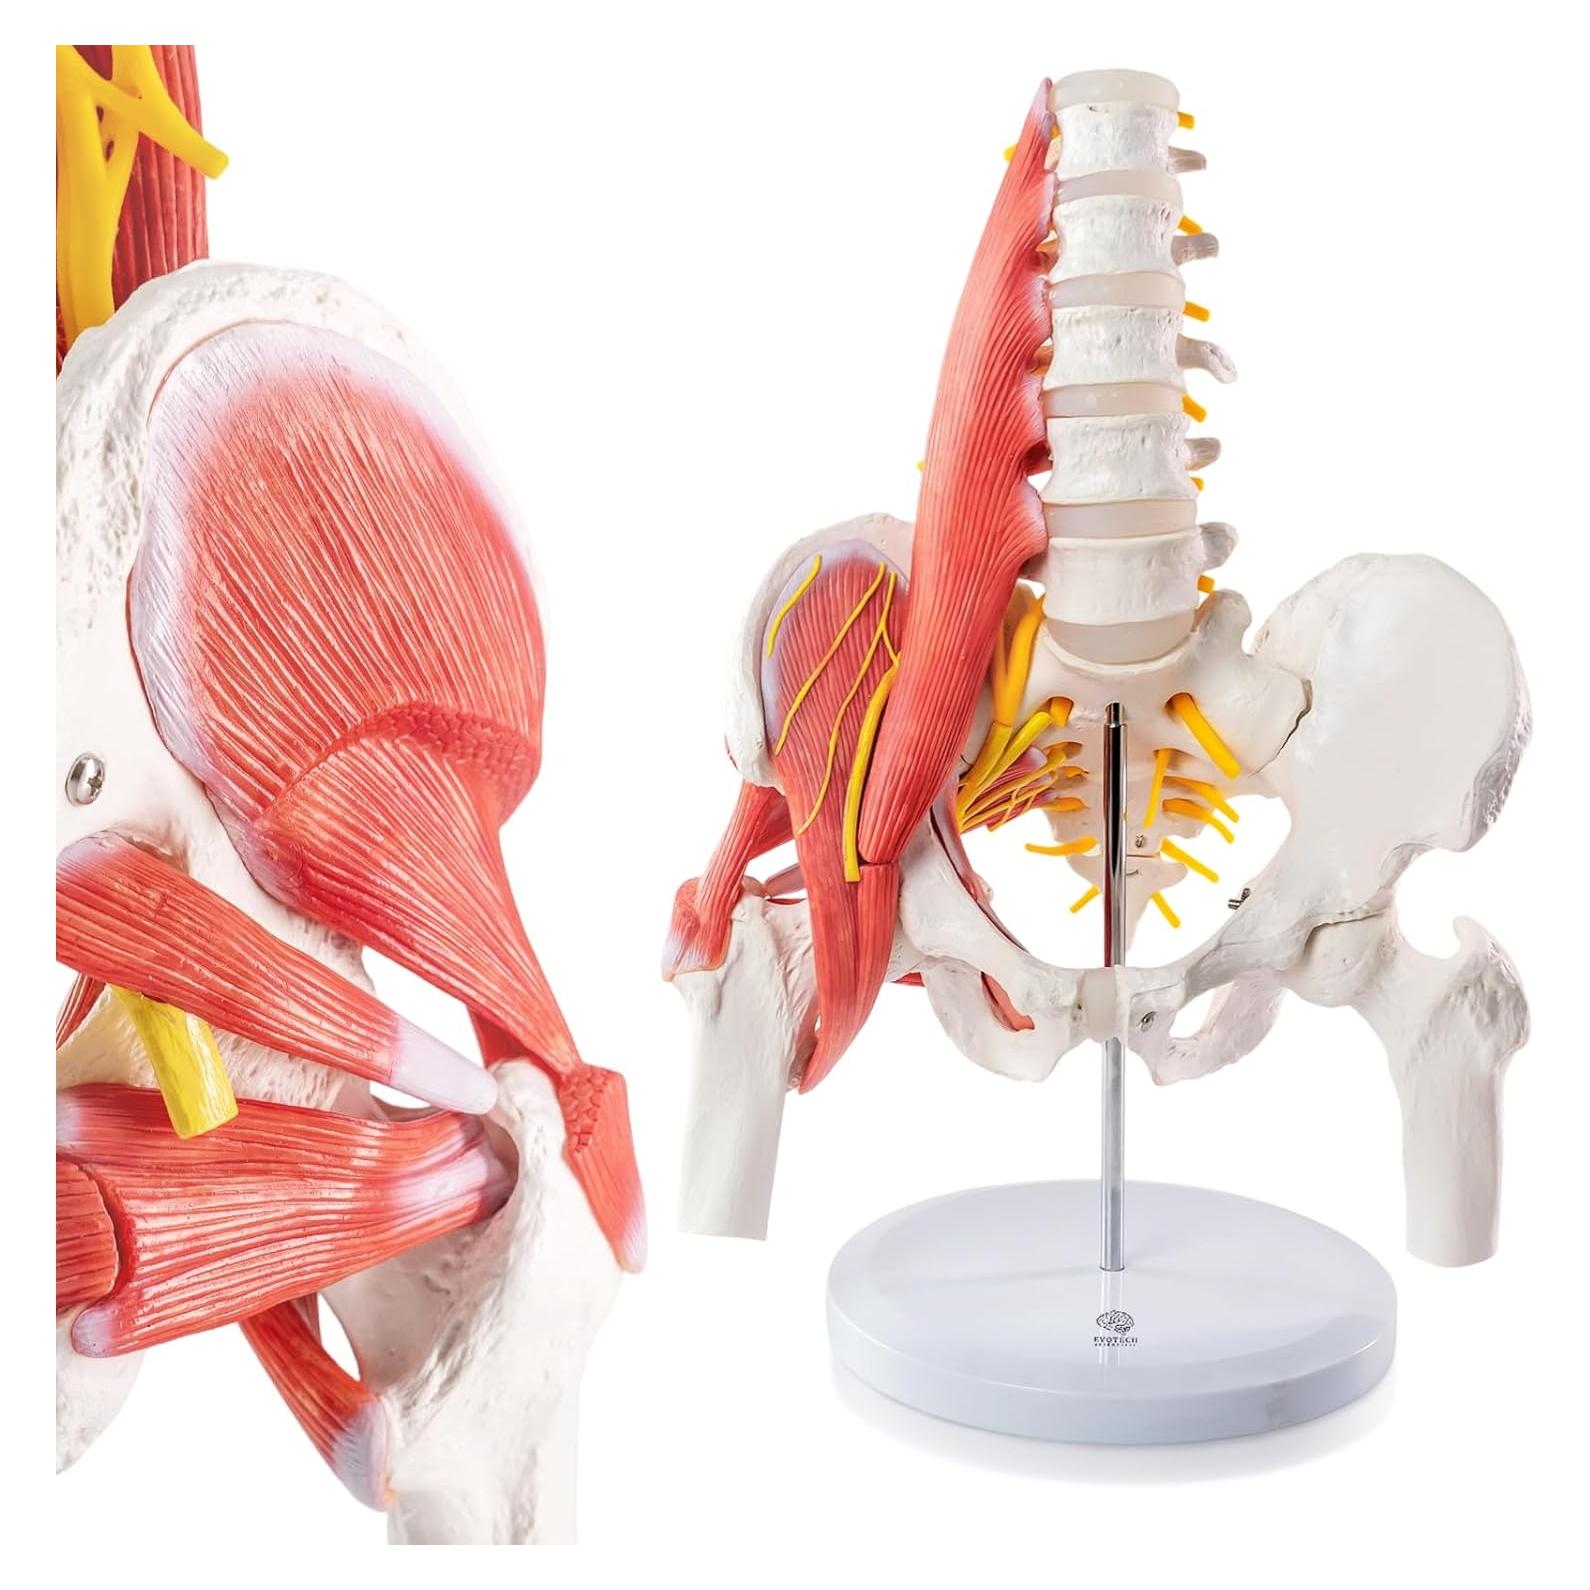

Modelos Anatómicos de Órganos marca Evotech (20 productos)

Modelos Anatómicos 3D EVOTECH SCIENTIFIC - Cuerpo, Corazón y Esqueleto